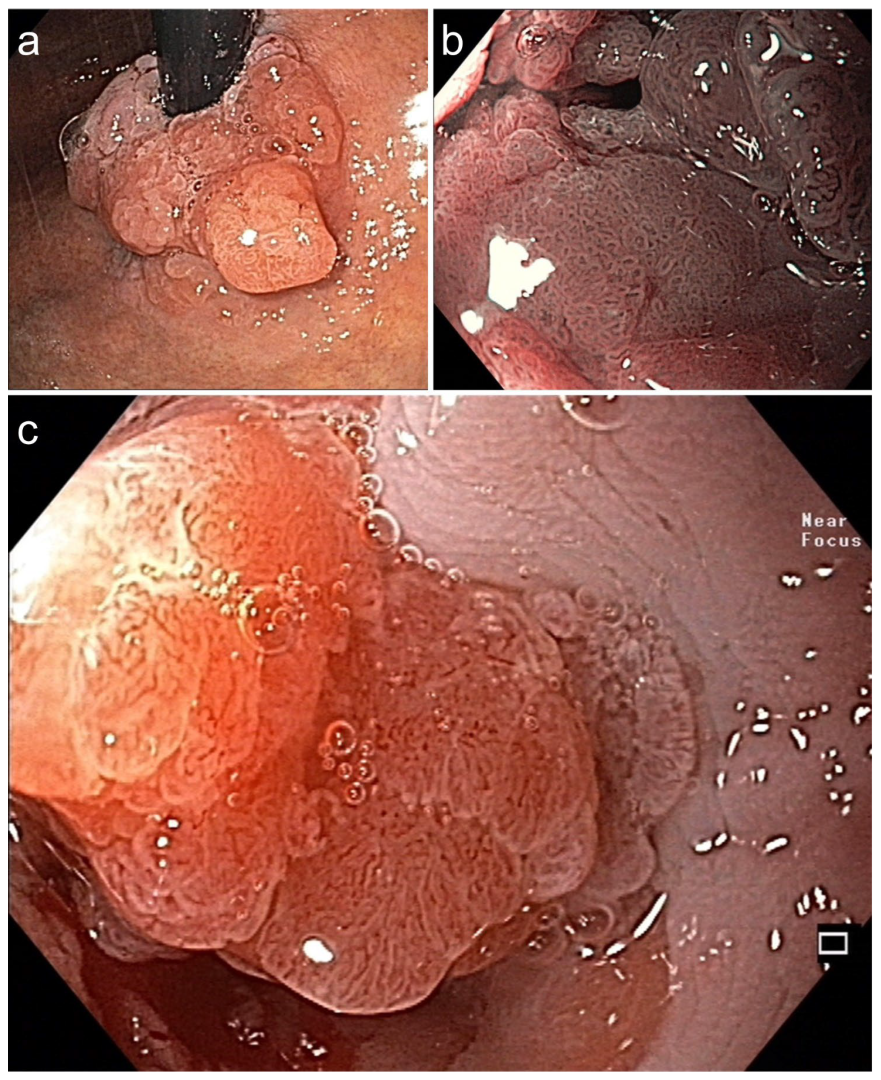

Figure 3. Symptomatic circular Barrett adenocarcinoma 0-IIa+Is for diagnostic ESD en bloc (16.6 × 6 cm). (a) in the cardia (WLI, retroflex view) and (b) in stenosis (BLI, 40×, prograde: dense VP & SP). (c) Dense SP (regular epithelial white zone) & VP with V/S concordance (WLI 60×). Histopathology: AC, G1 pT1a, m2 L0 V0 pN0 Bd1, R curative. Died at age 87 from pneumonia, DFS 5.3 yrs.